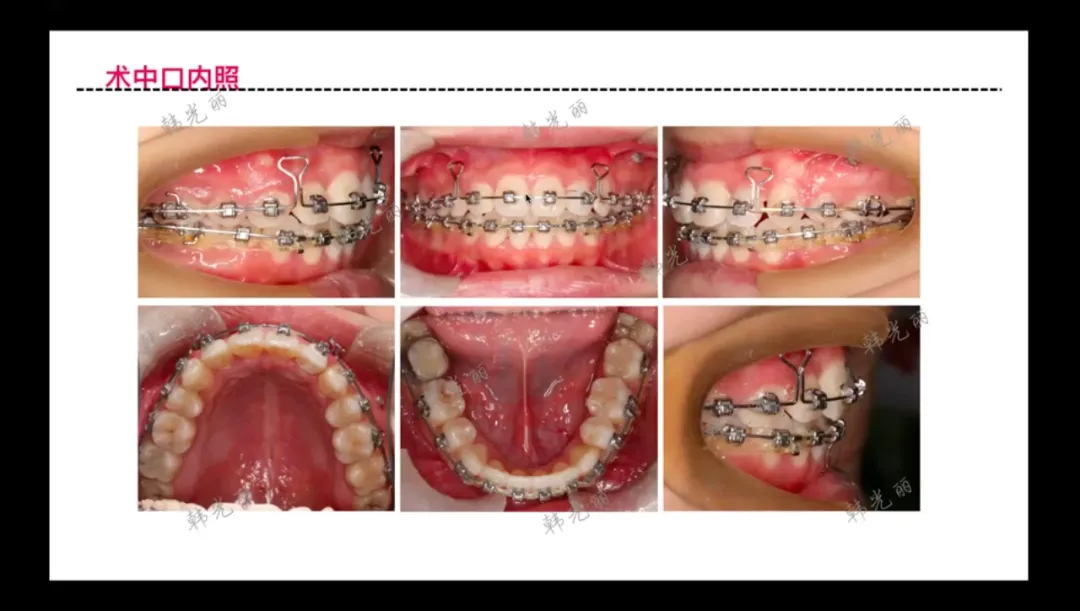

9)个性化诊断策略实战:

• 横腭杆提供主要支抗控制

• 种植钉用于精确控制前牙移动方向

• 采用滑动法关闭拔牙间隙

• 尖牙首先达到中性关系(实际出现超中性移动)

• 原因分析:未及时取下尖牙上的太白Y形牵引装置

• 间隙关闭技术

• 尖牙过度后移通过带环系统补偿

• 最终面型改善显著(下唇仍轻度外翻)

• 种植钉主要改变牙根生物力学方向

• 实现前牙控根移动和牙槽骨改建